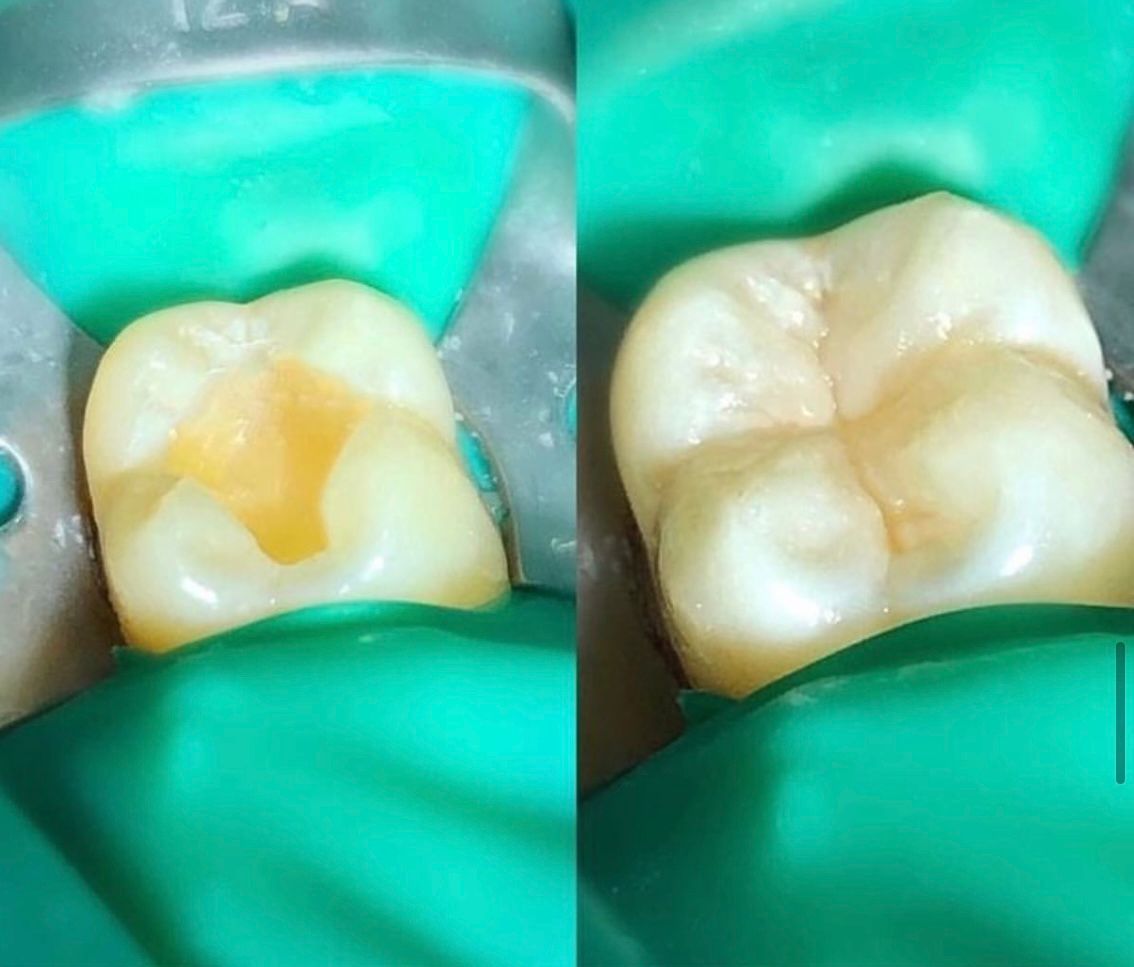

Restauraciones Adhesivas o Incrustaciones dentales

Resinas dentales

Cementado de incrustación/coronas

Cambio de restauración defectuosa (Resina o Amalgama)

Aplicación de incrustación estética